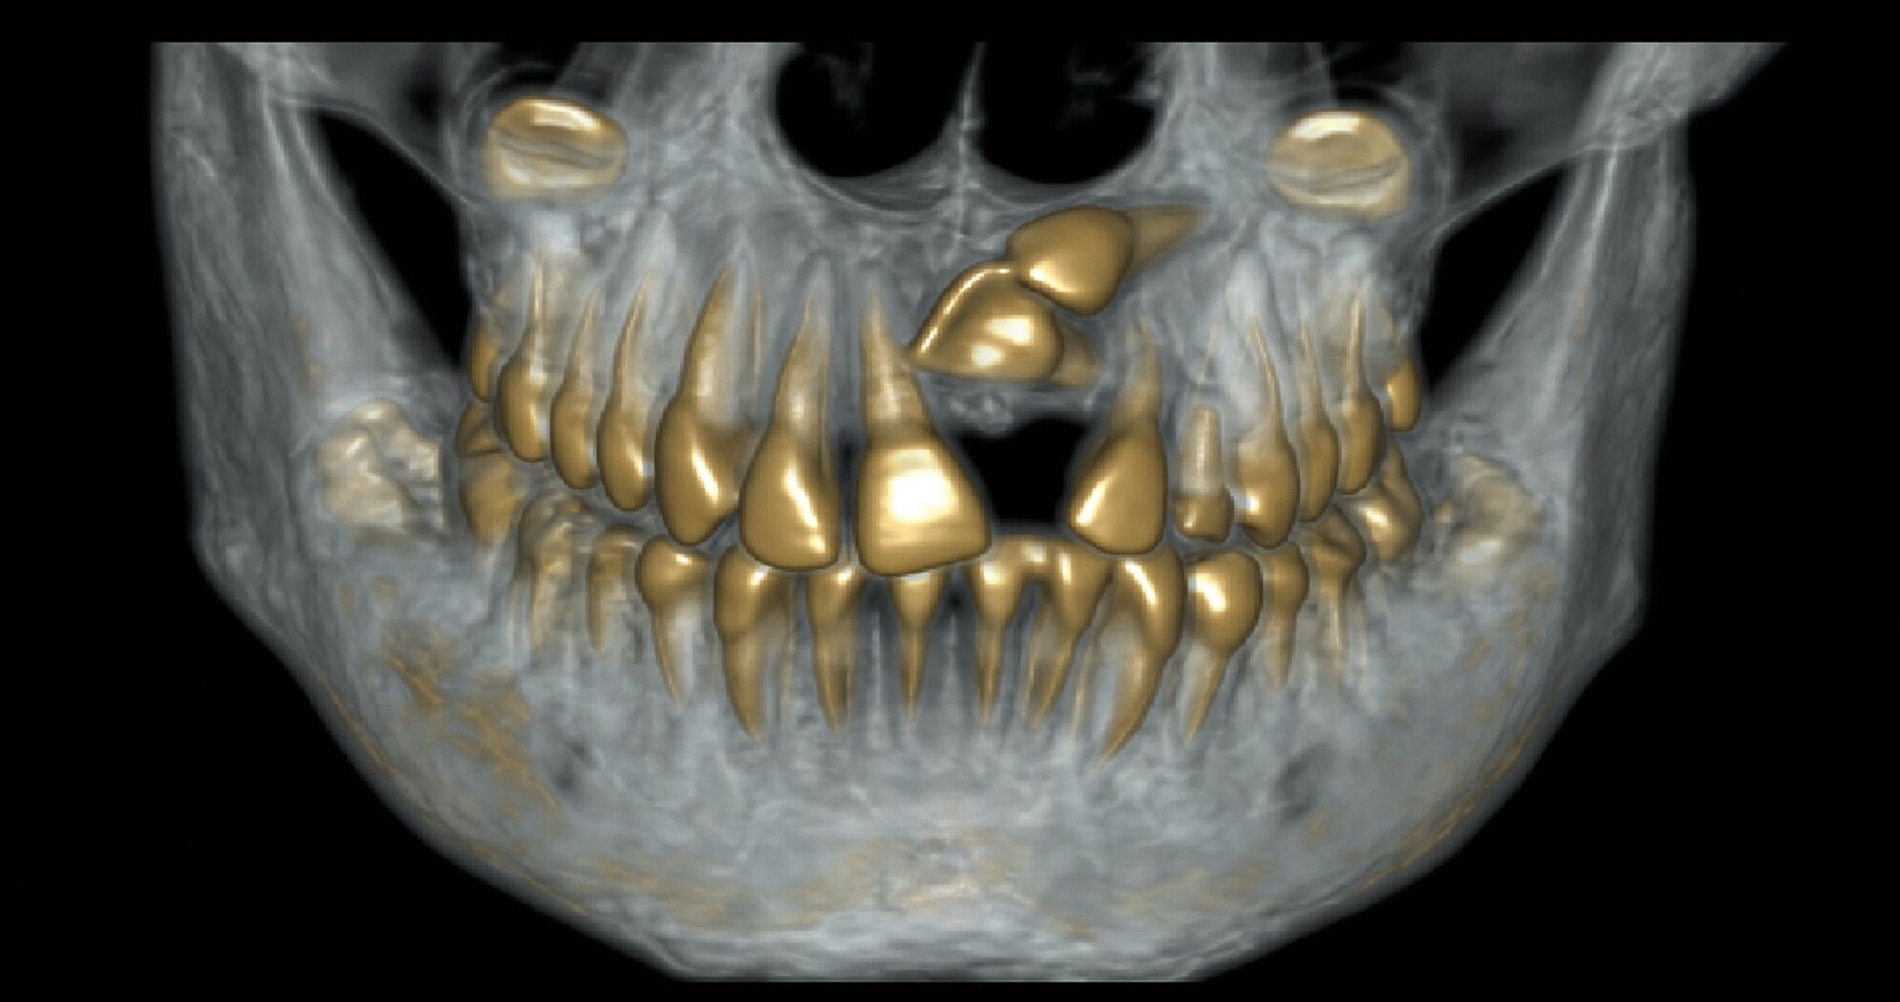

Die kieferorthopädische Behandlung der Patientin wurde im Mai 2018 (alio loco) begonnen. Zu diesem Zeitpunkt war die Patientin zehn Jahre alt. Bei der Erstellung des Behandlungsplans wurde der Fall initial als fehlender linker Eckzahn im Oberkiefer diagnostiziert. Vor der Extraktion des Schneidezahns wurde eine CT-Aufnahme durch den Erstbehandler angewiesen. Die Bildgebung ergab, dass der obere mittlere Schneidezahn sowie der Eckzahn auf der linken Seite betroffen waren (Abbildung 1). Die Patientin wurde daraufhin vom Erstbehandler zur Extraktion des impaktierten Zahnes 21 überwiesen.

Im Februar 2019 wurde die kieferorthopädische Klinik von der Erstautorin übernommen. Bei der Auswertung der vorgefundenen Daten der Patientin wurde festgestellt, dass der linke obere zentrale Schneidezahn vor sechs Monaten extrahiert worden war. Die festsitzende Apparatur war im Oberkiefer bereits eingegliedert. Die Druckfeder zwischen Zahn 11 und 22 diente zur Lückenöffnung für den späteren prothetischen Ersatz des Zahnes 21. Auch auf den persistierenden linken Milcheckzahn war ein Bracket geklebt. Die Okklusion im Bereich der ersten Molaren war rechts und links neutral (Abbildung 2).